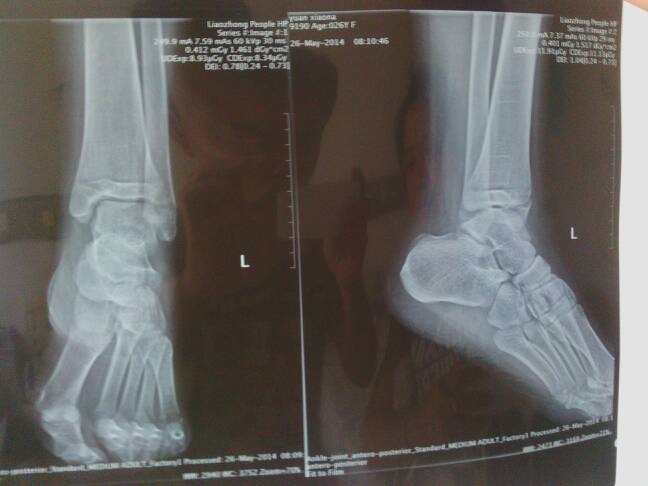

敬请老专家解疑。左内踝骨折,石膏外固定,4日初诊与14日复查时拍的片子一样位置很好。一个月经大夫允许开始拄拐下地轻微锻炼。  次月13日(已39天)复查拍片显示内踝侧面长的挺好,前踝向下移位约2~3毫米,主治医师说没事,又挺了十多天(次月26日)拍片还是一样依旧错位。   医生有的说没事,有的说应该手术弄不好还要移骨,(怕留后遗症)唉,搞得我头都大了!请经验丰富的老教授、专家帮帮我吧!

骨折稍微有移位,估计以后踝关节活动会有点缺陷。但是具体有没有太大影响不好说,因为我也见过有些人的片子看起来关节都毛糙了,患者却说不痛。因人而异吧,最好做个CT三维重建。我的建议是先继续保守治疗,暂时最好先不要下地活动。饮食上要多摄入含钙的食物和维生素含量高的食物。